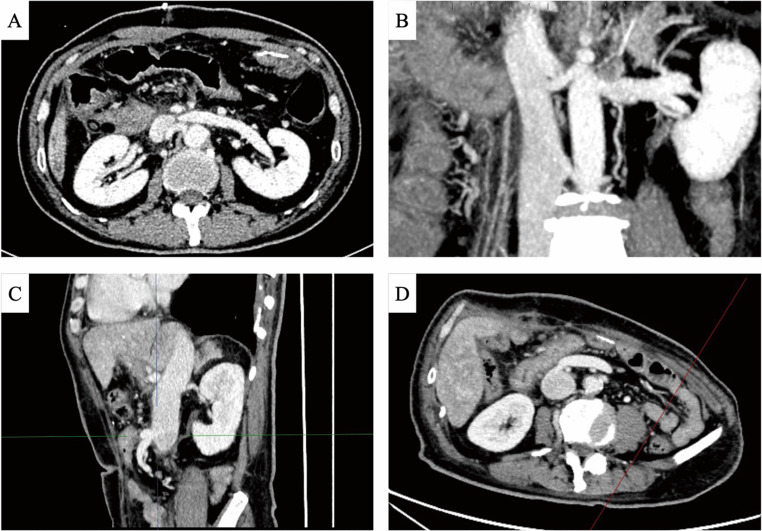

Purpose: In pancreaticoduodenectomy, extensive involvement of the superior mesenteric vein (SMV) often complicates venous reconstruction, especially when artificial grafts are unavailable. In such cases, meso-caval shunt (MCS) emerges as a solution. This study aimed to evaluate the safety and efficacy of permanent MCS as both an emergency procedure and a planned surgical strategy.

Methods: We retrospectively analyzed 8 consecutive patients undergoing pancreaticoduodenectomy with permanent MCS between July 2019 and January 2025 at our institution. Clinicopathological characteristics were identified using electronic medical records, and the same surgeon performed all surgeries.

Results: The study included seven cases of pancreatic cancer and one ampullary carcinoma (6 male, 2 females; age 54-71 years). The mean operative duration was 510 min with 767 ml blood loss. All patients achieved R0 resection with minor complications (Clavien-Dindo grade I/II), no mortality, and preserved portal perfusion. Meso-caval shunt patency was confirmed postoperatively without hepatic dysfunction. Median survival reached 21 months.

Conclusion: Permanent MCS is a reliable elective option for venous reconstruction in pancreaticoduodenectomy, especially when graft-based solutions are not available. Its success in achieving R0 resection while maintaining portal hemodynamics suggests its utility in complex pancreatic resections.